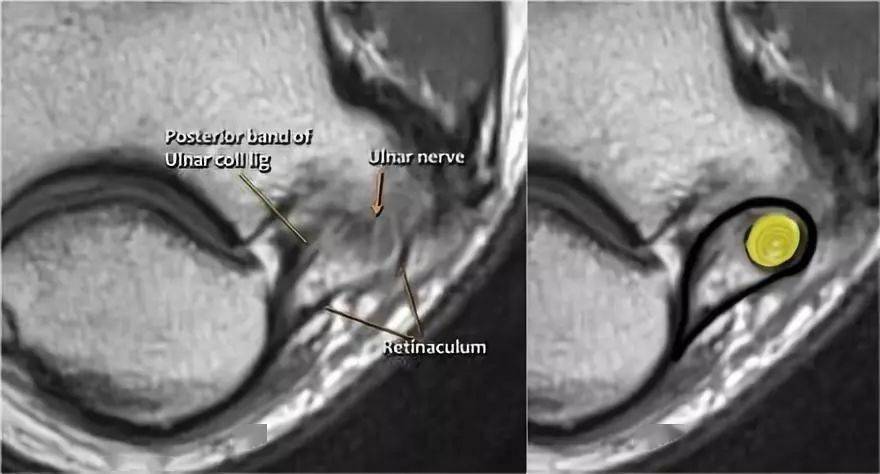

肘关节常见病的mri图谱详解